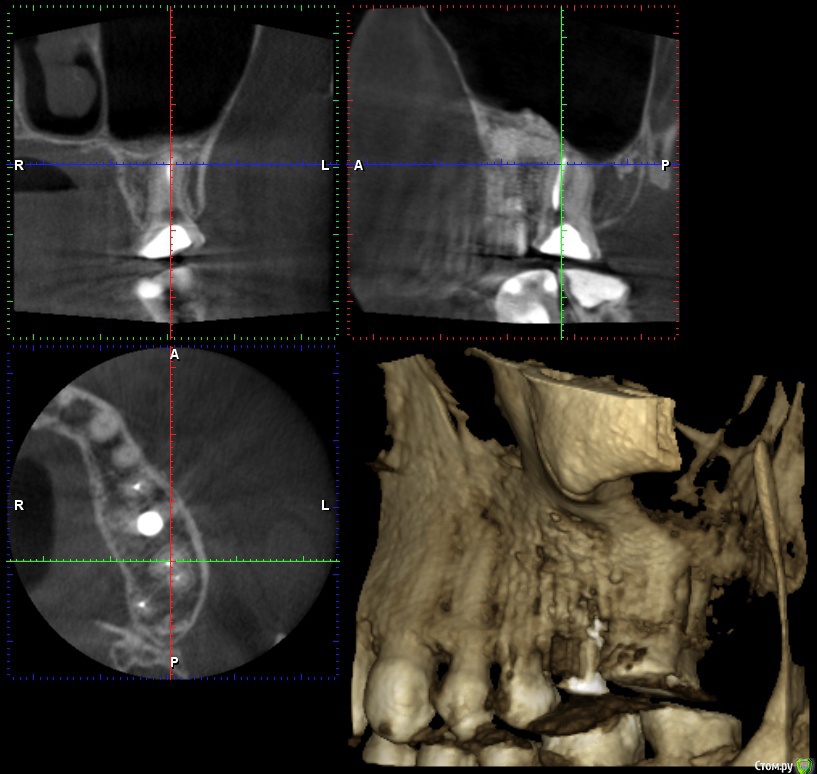

wladdX Опубликовано 26 января, 2017 Поделиться Опубликовано 26 января, 2017 Несколько скринов 2-й сегмент. Ссылка на комментарий

wladdX Опубликовано 26 января, 2017 Поделиться Опубликовано 26 января, 2017 (изменено) 3-й сегмент. Изменено 26 января, 2017 пользователем wladdX Ссылка на комментарий